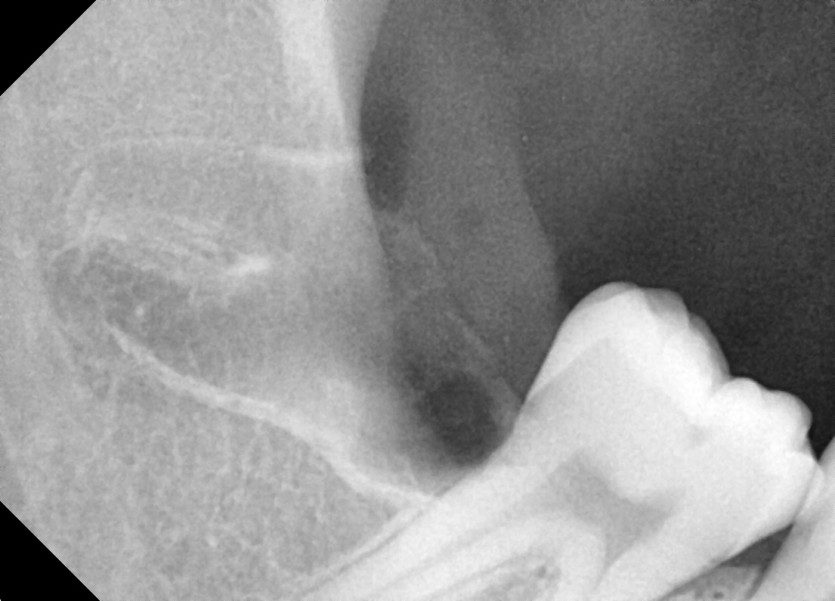

#18,48 사랑니 발치

구강 외과 전문의가 당일 발치했습니다.